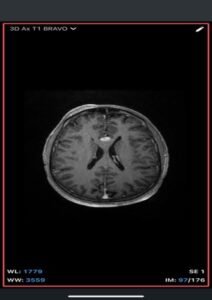

Imaging Findings-

- MRI

- T1-weighted: Hyperintense (fat signal).

- T2-weighted: Variable, usually hyperintense; may show chemical shift artifacts.

- Fat-suppressed sequences: Complete signal suppression confirms fat composition.

- Post-contrast: No enhancement.

- Often associated with:

- Corpus callosum agenesis/dysgenesis